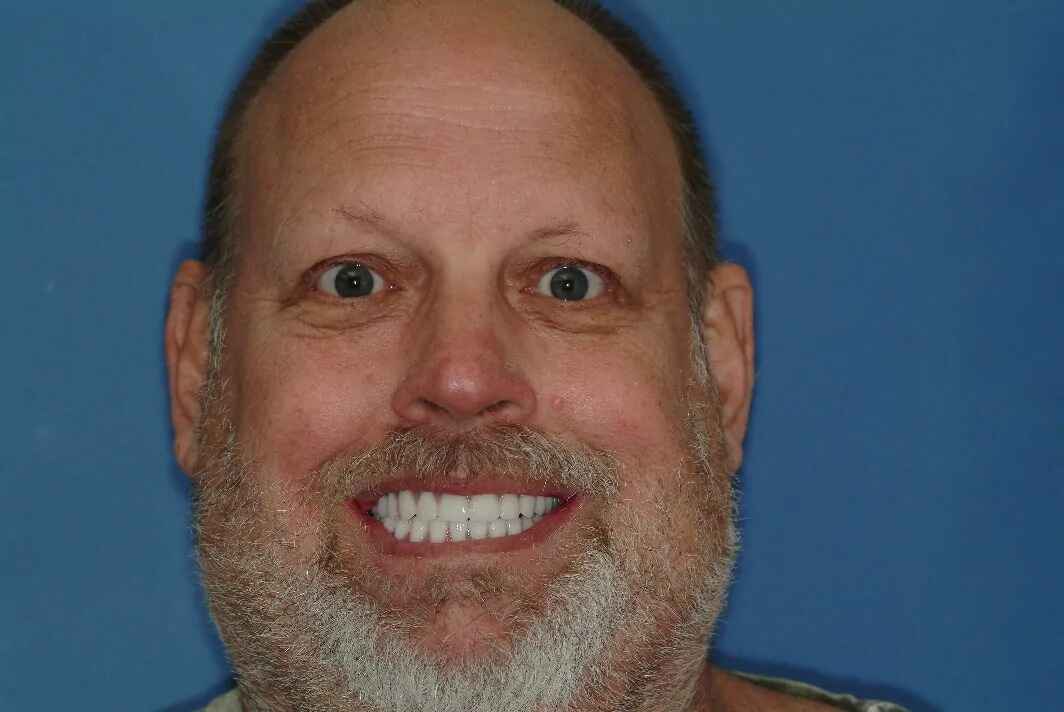

Ben’s Procedure

Ben had gaps and uneven teeth. This is a prepless veneers case. The teeth were not touched. Dental veneers were cemented without prepping teeth.